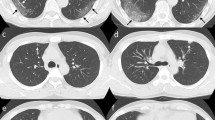

Ground-glass opacities with positive DWI. 58-year-old male. a End-inspiratory axial CT, b Free-breathing PD-weighted axial image, c Apparent Diffusion Coefficient Map, and d) DWI free breathing (b = 1000 s/mm2). Note an area of GGO on the left lower lobe that shows restricted diffusion on DWI and hyperintensity on ADC map, corresponding to an area of acute inflammation

The imaging findings assessed on MRI and CT scans for this study are summarized in Table 2. The predominant patterns of parenchymal involvement according to CT versus MRI were: GGOs in 27 of 52 cases (51.9%) vs. 32 of 52 cases (61.5%), interlobular septal thickening in 17 of 52 cases (32.7%) vs. 17 of 52 cases (32.7%), and consolidation in two of 52 cases (3.8%) vs. two of 52 cases (3.8%). At least one additional finding was present in 41 of 52 cases (78.8%) according to CT and in 47 of 52 cases (90.4%) according to MRI. No pulmonary findings were observed in five of 52 cases (9.6%) using CT and in one of 52 cases (1.9%) using MRI. DWI was positive for high suspicion of inflammatory activity in 23 to 50 cases (46.0%); 19 of whom also had GGOs (Fig. 1). Agreement between CT and MRI when evaluating the presence of different imaging findings, as assessed with Cohen’s k, was very high for consolidation (k = 1.000); substantial for interlobular septal thickening (k = 0.734); poor for GGOs (k = 0.339), fibrotic changes (k = 0.224), pleural indentation (k = 0.231), vessel enlargement (k = 0.339), and bronchiolar ectasia (k = 0.000). The degree of agreement between CT and MRI in identifying the predominant pattern was substantial (k = 0.764).

The sensitivity, specificity, accuracy, and positive and negative predictive values of MRI, when considering CT as the standard of reference, in the detection of different parenchymal patterns are detailed in Table 3. The sensitivity was highest for interlobular septal thickening (1.00, 95% confidence interval (CI): 0.91–1.00), consolidation (1.00, 95% CI: 0.63–1.00), and GGOs (1.00, 95% CI: 0.91–1.00) (Fig. 2). Conversely, MRI showed poor sensitivity in the detection of fibrosis (0.18, 95% CI: 0.04–0.43), pleural indentation (0.23, 95% CI: 0.09–0.44), vessel enlargement (0.50, 95% CI: 0.07–0.93), and bronchiolar ectasia (0.00, 95% CI: 0.00–0.18). Specificity was overall very high, except for GGOs (0.25, 95% CI: 0.05–0.57) and interlobular septal thickening (0.64, 95% CI: 0.31–0.89). MRI was not able to detect bronchiolar ectasia in any of the cases.